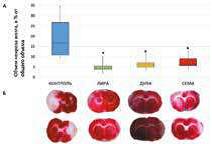

В рамках гранта РНФ «Экспериментальное изучение нейропротективных свойств современных сахароснижающих препаратов» выполнено экспериментальное исследование инфаркт-лимитирующего действия и влияния на неврологический статус арГПП-1 разной продолжительности действия (лираглутида, семаглутида, дулаглутида), а также иНГЛТ-2 разной степени селективности (эмпаглифлозина и канаглифлозина) у животных без СД с транзиторной фокальной ишемией головного мозга. Установлено, что все препараты обладали сопоставимой способностью сокращать объем повреждения головного мозга, однако только арГПП-1 способны уменьшать выраженность неврологического дефицита.

Anna Murasheva, Oksana Fuks, Natalya Timkina, et al. SGLT-2 Inhibitors’ and GLP-1 Receptor Agonists’ Influence on Neuronal and Glial Damage in Experimental Stroke // Biomedicines. — 2024. — Vol. 12, № 12. — 2797. IF 4,1. DOI: 10.3390/biomedicines12122797. Режим доступа: https://doi.org/10.3390/biomedicines12122797